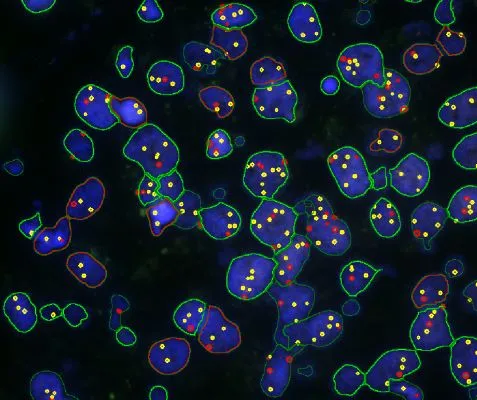

Case Study: Analysis of FISH Using Tissue Cytometry

The IF Dots App in StrataQuest streamlines automated analysis of FISH stainings by detecting nuclei and quantifying dots per cell. This case study shows how the workflow enables accurate, exportable data for genetics research and clinical applications.

Understanding the Different Types of FISH Evaluations

FISH is a powerful imaging-based technique for detecting DNA and RNA sequences directly in cells and tissues. This post explores the advantages of FISH, its complementary methods like CISH and RNAscope, and how TG solutions streamline automated FISH analysis.

How FISH Image Analysis Factors into Next-Gen Digital Pathology

How does FISH image analysis advance digital pathology? Learn how whole-slide imaging and AI-powered algorithms enable fast, accurate detection of chromosomal abnormalities, streamline workflows, and open new possibilities for precision medicine.

Quantitative Image-based Cytometry: Focus on the Foci!

Prof. Nicolas C. Hoch, University of Sao Paulo, is presenting his research on signaling and repair of DNA damage. He and his group are utilizing the power of TissueFAXS i PLUS slide scanning and the high-end image analysis solution, StrataQuest, for their research.